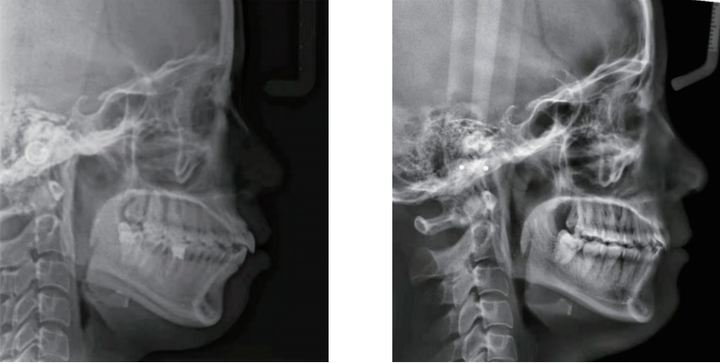

矫正行动:比如高角骨性下巴后缩,我们更多的希望是逆时针旋转,因此牙齿矫正过程中,我们要做好对上前牙的转矩控制,同时上牙不能过长,下前牙必须要足够的压低,并且是直立于基骨,这样可以下巴不会后退。

如果想要引导下巴往前伸,还需要控制好后部的颌平面角度,颌平面一定是平的,不能是倾斜的,如果颌平面越斜,会让下巴后缩。通过这三点来改变下颌骨的位置,从而可以改善下巴后缩的问题。

矫正效果:成人不必焦虑年龄限制,明确主诉功能or美观,选择好正畸医生,制定合适的正畸方案。把咬合的一些因素去掉,把下巴行的情况,尽量引导出来,所以看起来下颌骨位置好了,有下巴了。

所以正畸医生做的就是这三点:上前牙的位置的控制,下前牙位置充分直立,还有颌平面的角度调整,通过这三点来改变下颌骨的位置,从而可以改善下巴后缩的问题。